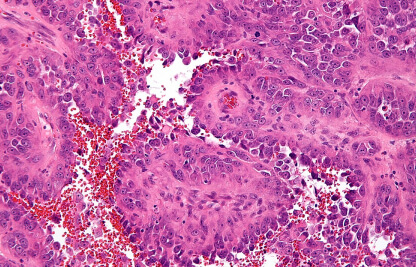

ΠΊΠ°Ρ€Ρ‚ΠΈΠ½ΠΊΠ° Π»ΠΈΠΌΡ„ΠΎΠΌΡ‹

ΠœΠ°ΡΡ‚ΠΎΡ†ΠΈΡ‚ΠΎΠΌΠ°

ΠœΠ°ΡΡ‚ΠΎΡ†ΠΈΡ‚ΠΎΠΌΠ° — это ΠΎΠΏΡƒΡ…ΠΎΠ»ΡŒ ΠΈΠ· Ρ‚ΡƒΡ‡Π½Ρ‹Ρ… ΠΊΠ»Π΅Ρ‚ΠΎΠΊ. ΠžΡ‡Π΅Π½ΡŒ распространСна Ρƒ собак, особСнно Ρƒ боксСров ΠΈ Π±ΡƒΠ»ΡŒΠ΄ΠΎΠ³ΠΎΠ².